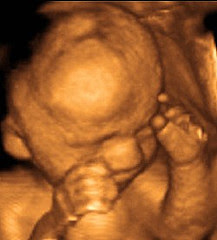

Bu hafta içinde de bebeğinizin beyin dokusu hızlı gelişimini sürdürüyor ve akciğerler de gelişimlerine devam ediyorlar. Bebeğiniz bu haftadan itibaren gözlerini açıp kapama hareketleri yapmaya başlayacak.Bebeğiniz bu haftanın sonunda yaklaşık 950 gram olacak. Ancak sizin ve eşinizin yapısal özelliklerine göre bu 650 gram kadar düşük olabileceği gibi, 1500 gram kadar yüksek olabilir. Eğer bebeğinizin ölçüleri bu haftada "biraz düşük" gibi görünüyorsa hemen endişelenmeyin. Bu konuda doktorunuzun size önerdiklerine (sol yana yatarak bol bol istirahat etme, belli gıdaları daha fazla tüketme gibi) mutlaka uyun. Belli bir süre sonunda yapılan ölçümlerde büyük ihtimalle bebeğiniz sizin arzu ettiğiniz kiloya ulaşacaktır. Yine de tüm bebeklerin aynı kiloda doğmadıklarını, sağlıklı doğan bebeklerin doğum kilolarının 2500-4000 gram gibi geniş bir yelpazede yer alabildiğini unutmayın.

Bebeğinizin Göz Gelişimi

Gözler ilk olarak embriyonun gelişiminin 22. gününde ortaya çıkar. Başlangıçta gelişmekte olan beynin her iki yanında bulunan bir çift koyu renkli oyuğa benzerler. Bu oyuklar gelişmeye devam ederler ve sonunda "optik gözecik" adı verilen çukurlara dönüşürler. Her bir gözün merceği ektodermden oluşur.

Gelişimin ilk evresinde gözler başın yan tarafında bulunur. Hamileliğin 7. ve 10. Haftaları arasında yüzün ortasına doğru haraket ederler. Hamileliğin 8. Haftasında göze giden kan damarları oluşur. Hamileliğin 9. Haftası boyunca gözdeki yuvarlak bölge olan gözbebeği oluşur. Bu dönemde optik sinir olarak isimlendirilen gözlerden beyne giden sinir bağlantısı oluşur.

11. ve 12. Haftalar arasında oluşan gözkapakları birbirine yapışıktır. Hamileliğin 27. ve 28. Haftalarında açılıncaya kadar birbirlerine yapışık kalırlar.

Gözün arka bölümündeki retina ışığa duyarlıdır. Gözde, ışık görüntülerinin odaklandığı bölgedir. Normal tabakalar hamileliğin 27. Haftasında oluşur. Bu tabakalar ışık ve ışık bilgisini alarak beyine iletir. Bu, görüntü olarak adlandırılır.

Bu haftanın sonunda bebeğinizin boyu yaklaşık 35 cm. ve ağırlığı yaklaşık 950 (650-1500) gram!